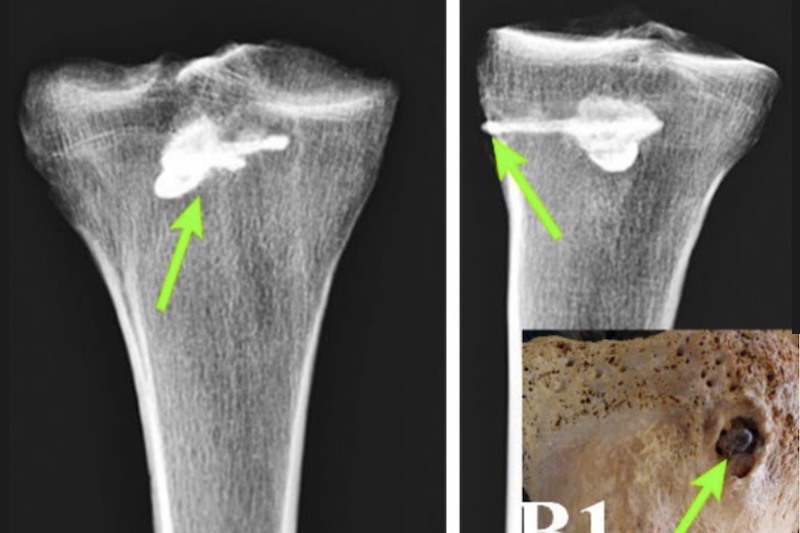

Araştırmanın odak noktası, iskeletin sağ kaval kemiğine (tibia) derinlemesine saplanmış olan demir ok ucuydu. Kemiğin tahrip edilmemesi amacıyla XRF (X-ışını floresansı) ve Quantometer gibi zarar vermeyen test yöntemleri kullanıldı.

Bilgisayarlı Tomografi (BT) taramaları, kemiğin içinde metalik bir nesnenin varlığını gösteren 4000 Hounsfield birimi değerini ortaya çıkardı.

Paleopatoloji incelemeleri, ok yarasının şiddeti hakkında önemli ipuçları verdi. Ok, kaval kemiğine son derece isabetli bir şekilde saplanmış olmasına rağmen, görüntüleme çalışmaları ok yarasının yakınında tipik kırık veya deformasyon belirtilerinin olmadığını gösterdi. Bu durum, silah kullanımında dikkate değer bir isabet olduğunu kanıtlıyor.

Daha da önemlisi, ok ucunun etrafındaki kemik yapısı, bireyin bu yaralanmadan sonra yaşamaya devam ettiğini gösteren iyileşme işaretleri sergiliyordu. Ok ucunun saplandığı bölgenin etrafındaki kemik dokusu, zamanla yoğunlaşarak kompakt kemiğe dönüşmüştü. Tibia’nın ok ucunun girdiği yer olan tibial tüberozite bölgesinde 11.6 mm çapında yuvarlak, kompakt yeni kemik oluşumu gözlemlendi. Ayrıca, ok ucu çevresinde enfeksiyon belirtisi (yeni kemik büyümesi veya deformite) olmaması, o dönemin tıbbi ve ilaç uygulamaları hakkında kapsamlı bir anlayışa sahip olunabileceğini düşündürüyor.

Ancak, tüm bu teknolojik ve iyileşme kanıtlarına rağmen, ok ucunun kemiğe saplanmış olduğu yerden çıkarılamamış olması, Part toplumunun cerrahi uygulamalarındaki kısıtlamaları ve eksiklikleri ortaya koyuyor. Araştırmacılar, ok ucunun vücut yüzeyine nispeten yakın konumda olmasının çıkarılmasını mümkün kılabileceğini, ancak başarılı olunamadığını belirtiyor.